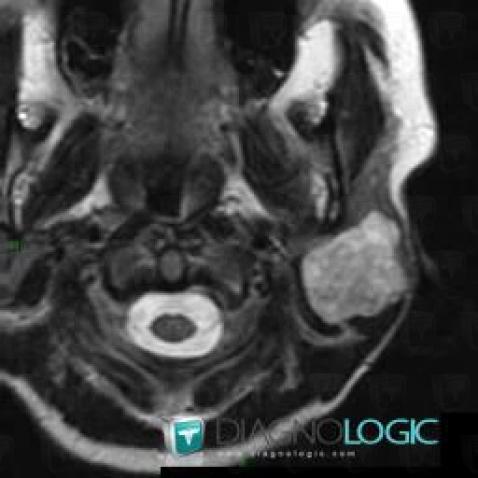

Pleomorphic adenoma, Parotid and other salivary glands, MRI

Here is the specific information in the key image above:

- Diagnosis Pleomorphic adenoma, Location(s) Parotid and other salivary glands, with gamuts Cystic parotid gland lesion